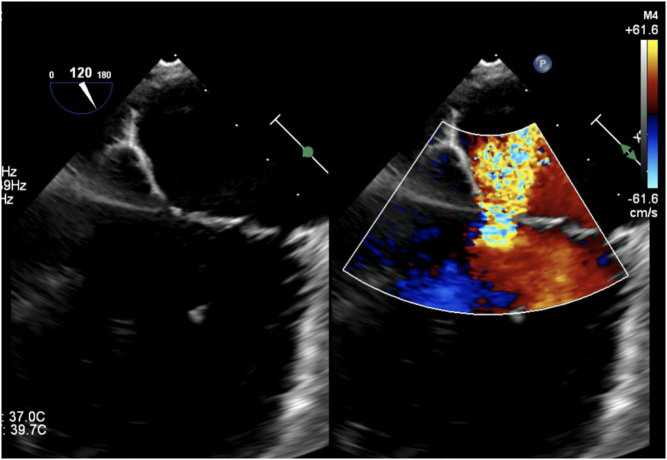

A 2D echocardiogram showed eccentric moderate mitral regurgitation. Right heart catheterization was performed and demonstrated elevated right and left filling pressures and mildly elevated pulmonary pressures with venous congestion. To further evaluate the severity and etiology of the mitral regurgitation, a transesophageal echocardiogram was done, revealing severe mitral regurgitation with a ruptured chord and a markedly thickened, highly mobile chord (Fig. 2).

Figure 2.

Transesophageal echocardiogram demonstrating severe mitral regurgitation with eccentric, posteriorly directed jet.

Chordae tendineae rupture often leads to excessive leaflet mobility and prolapse of the leaflet tip into the left atrium during systole giving rise to a flail leaflet which then results in severe mitral regurgitation. Interestingly, the transesophageal echocardiogram of our patient did not reveal significant systolic excursion of the leaflets indicating prolapse or flail but did have a regurgitant jet indicative of severe mitral regurgitation. Unlike chronic mitral regurgitation where a compensatory increase in left atrial compliance and size helps to offset the increase in left atrial pressure from the regurgitant jet, acute mitral regurgitation often leads to a sudden rise in left atrial pressures with the rapid development of symptoms and hemodynamic compromise.